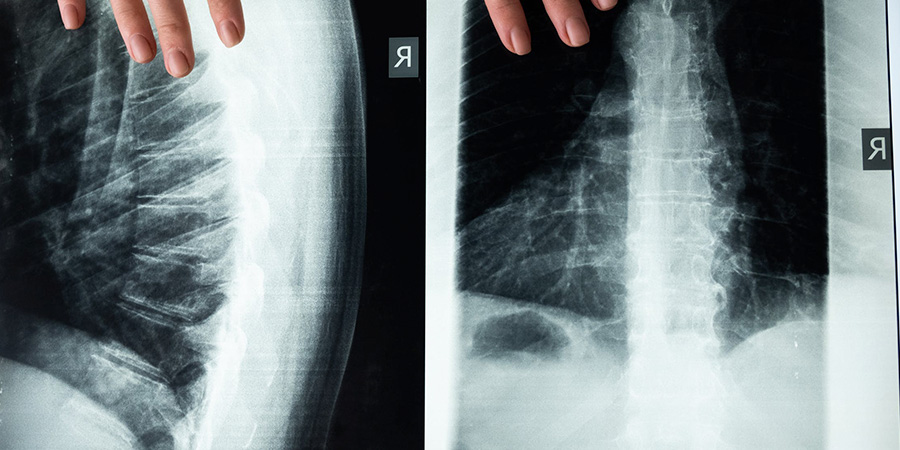

La endoscopia de columna avanzada tiene una duración que suele ser de 75 minutos. Este tiempo se divide en dos fases diferentes, una de aproximadamente 30 minutos y otra de 45 minutos. Durante esta primera fase de la operación se usan proyecciones anteroposteriores y laterales para identificar exactamente el abordaje que se llevará a cabo y la entrada de la cámara óptica endoscópica.